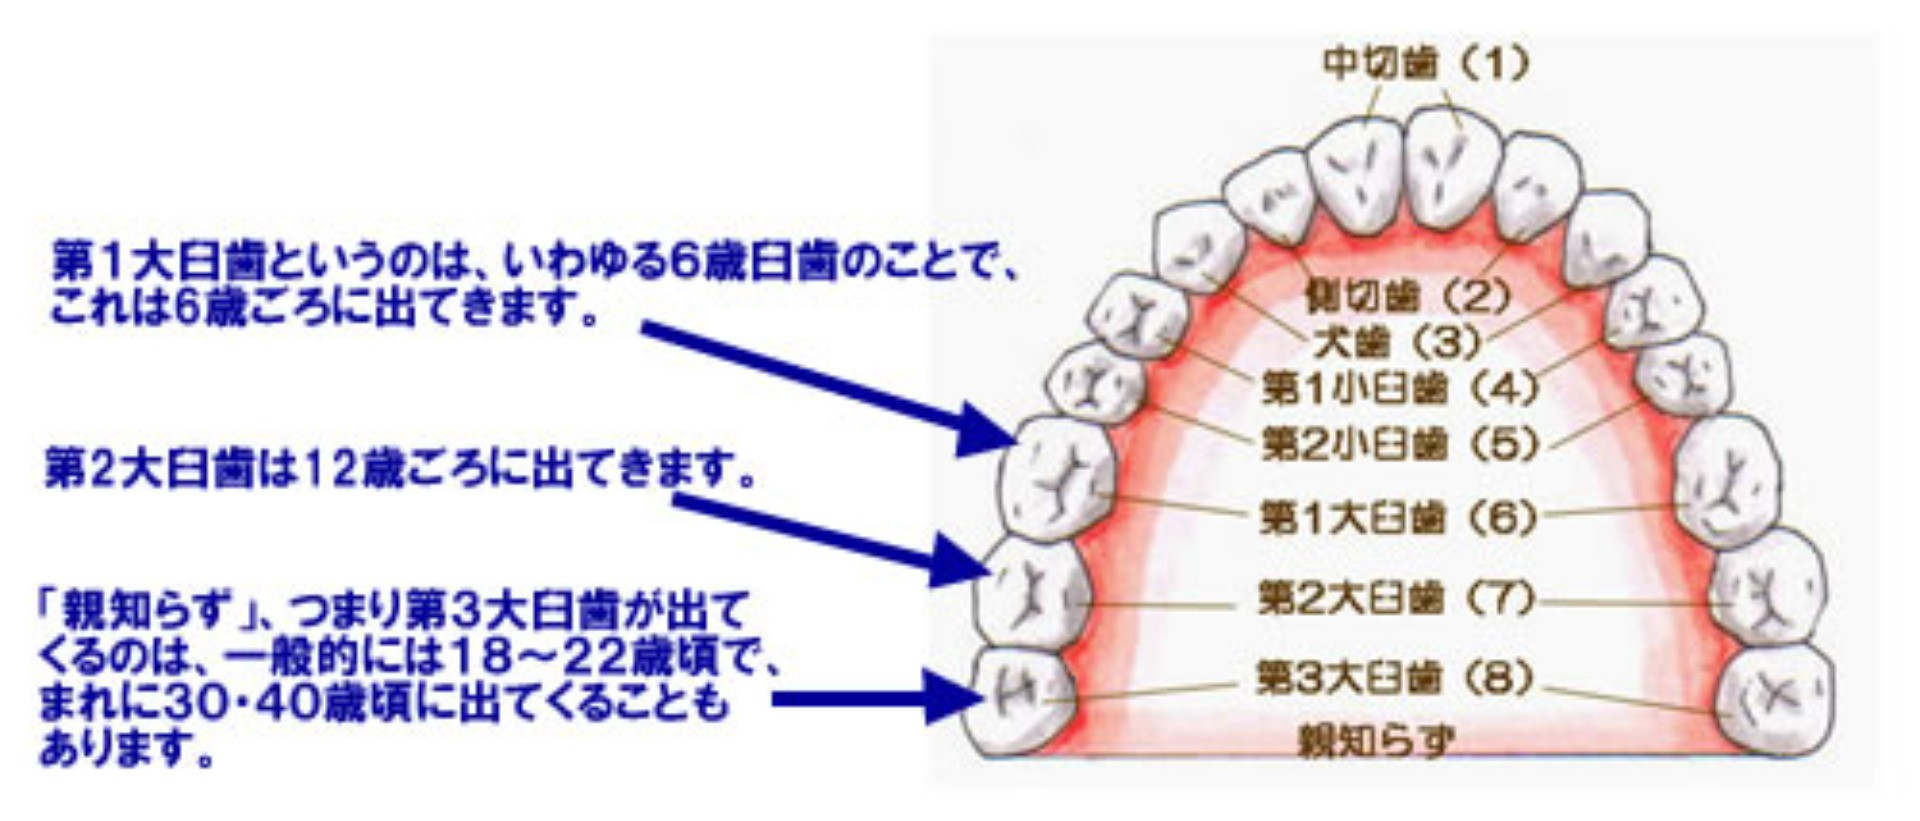

「親知らず」とは、「第3(だい3)大臼歯(だいきゅうし)」のことをいいます。 「親知らず」という呼び名の由来は、昔、「親が亡くなってから出てきたため」と言われています。また別名「智歯」とも言われています。これは

現代の人のアゴの骨は進化して小さくなってきています。しかし、歯の大きさは昔の人とあまり変わってはいません。ですから、最後に出てくる「親知らず」は、出てきたくてもスペースが狭く、正常には出てこない場合が多いのです。 下に挙げる図のように、一部分だけ頭を出しているだけであったり、斜めに傾いて出たり、アゴのなかで水平になったままのこともあります。 |